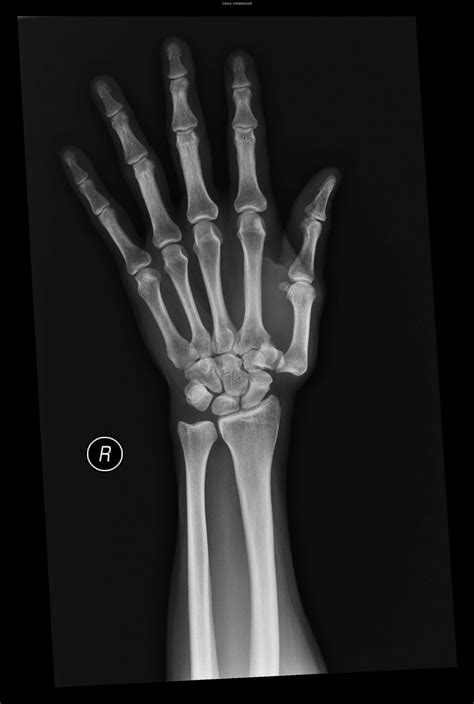

• X-rays: Standard imaging to look for joint space narrowing, bone spurs (osteophytes), and subluxation.

The first carpometacarpal joint, often referred to as the CMC joint of the thumb, is a marvel of human anatomy. It serves as the critical bridge between the trapezium bone in the wrist and the first metacarpal bone of the thumb. Because of its unique saddle-shaped configuration, this joint provides the thumb with an extraordinary range of motion, allowing for opposition—the ability to touch the tip of the thumb to the tips of other fingers. This function is essentially what differentiates human dexterity from that of most other primates, enabling us to grasp, pinch, hold tools, and perform intricate tasks with precision.

• carpometacarpal joint of right hand